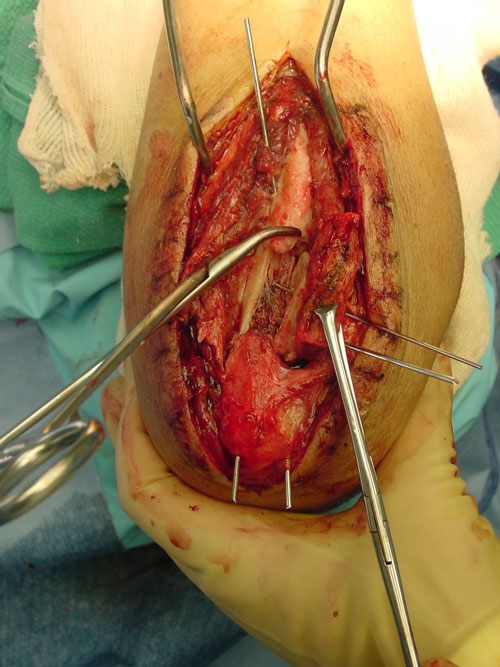

AC is a 25 year old male who was assaulted with a baseball bat. He sustained a shattered proximal ulna fracture with elbow dislocation. Surgery required application of a plate and screws, as well as pinning and cerclage wiring. He worked diligently in therapy to regain the excellent range of motion in his elbow as demonstrated in the photo with me.